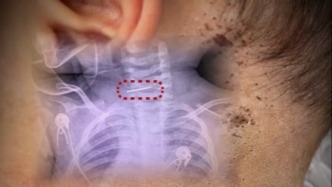

医生接诊发现“男婴颈椎藏针”,警方回应孩子生母精神状况称在开展核查00:47

医生接诊发现“男婴颈椎藏针”,警方回应孩子生母精神状况称在开展核查